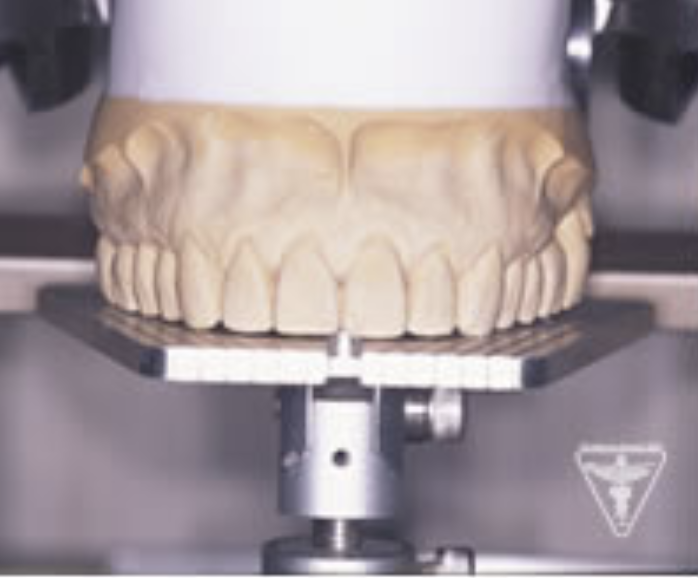

治療後

かみ合わせの深さを改善し、左下の骨を作り人工歯根で再構築しました。

前歯は、患者さんの希望でフルセラミックで対応しました。